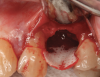

There are concerns that graft materials that fully resorb in a short timeframe may contribute to site collapse. Pure-phase beta-tricalcium phosphate (ß-TCP) (Figure 4) was one of the materials developed to address this concern. In a clinical and histologic study, extraction sockets were shown to have 91% of ridge width preserved when grafted with ß-TCP (Cerasorb®, Curasan, Inc., www.curasaninc.com) and covered with either a collagen or dense PTFE barrier.7 Dental implants were placed in these patients at 4 to 6 months postoperatively, a later time period than in the calcium sulfate studies. The patient shown in Figure 4 had only three maxillary teeth remaining, supporting an ill-fitting removable prosthesis. Due to the significant occlusal forces that were to be demanded on this single-tooth, implant-supported restoration, it was deemed advantageous to maximize the amount of vital bone in the recipient site. The area was left to heal for 7 months before flap exposure (Figure 5), implant placement in an ideal location, and graft analysis in the largest part of the defect. Analysis of the retrieved specimen showed 85% vital bone in the apical 90% of the core and a thin layer of nonresorbed ß-TCP at the crestal portion (Figure 6).

Fig 4. Pure-phase ß-TCP covered with a collagen barrier.

Figure 4